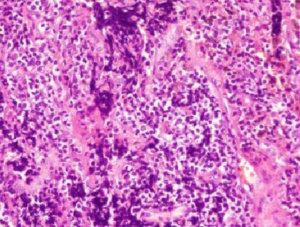

The patient underwent surgical treatment on October 14, 2015. Postoperative pathology identified small-cell lung carcinoma (SCLS) in the left lower lobe (Figure 1). Immunohistochemical staining was positive for Syn, CgA, CD56, TTF-1, CK (AE1/AE3), Hu antibodies (Table 1), and Ki67 (90%). Immunohistochemical staining was negative for LCA, P40, and CK5/6 was negative. Immunohistochemical staining was positive for Syn, CgA, CD56, TTF-1, and CK (AE1/AE3) (Figure 2). This patient was clinically diagnosed with a localized stage of small cell lung cancer and PNS. After surgery, numbness initially decreased but then started to return 3 days postoperatively. The patient received two cycles of chemotherapy (etoposide + platinum) with immune modulation during the period from October 2015 to December 2015. After each treatment, the patient’s numbness was alleviated for 2–3 days but then returned to baseline. The patient received radiation therapy, but this approach was discontinued because of bone marrow suppression. The patient’s numbness persisted, causing him to contemplate suicide. A multidisciplinary team prescribed pregabalin, bulleyaconitine A, amitriptyline, and duloxetine. This pharmacologic regimen alleviated the patient’s symptoms. The dosage of the four drugs were used for half a year according to the instructions, and the clinical symptoms were relieved 3 weeks later. This patient had been taking prabalinda orally for 1 year. No obvious adverse reactions or adverse events were observed. The patient had good compliance and no obvious adverse drug reactions. He is regularly followed-up in our hospital. After reexamination in the local hospital, there was no obvious abnormal disease in the patient. The patient remained alive and well at follow-up in December 2018. So far, patients have undergone chest CT and abdominal color Doppler ultrasound, showing that the tumor is stable, and the symptoms alleviated significantly.